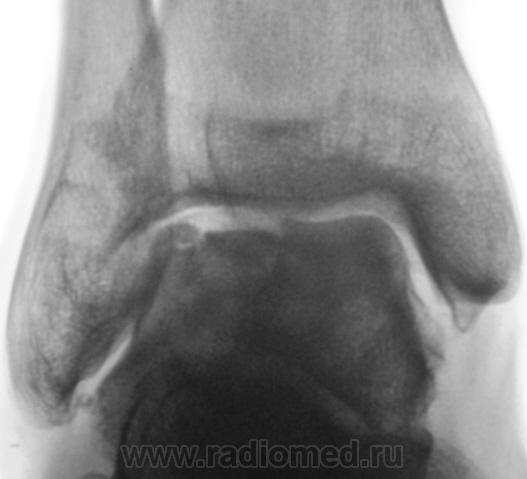

Пациент направлен на рентгенографию голеностопного сустава с диагнозом ДОА.

А присутствует линейный (или лентовидный, я их путаю) остеопороз, а это признак острого процесса.

Игорь Иванович, спасибо за книжные выдержки (никогда (пока?) не видел лентовидного остеопороза; кстати, и в наблюдении - не вижу)!

Так, всё же как? Считаете, что здесь артрит или остеомиелит, ИЛИ же остеопоротическая перестройка - сама по себе?..

Только не последнее...

+ за лентовидный остеопроз...

С учётом стрелочек, надо полагать, остеомиелит!..

Будем думать, что некроз блока таранной кости не такой уж и асептический, какая-то инхвекция там есть.

Посттравматический артроз с кистовидной перестройкойлатерального мыщелка Субхондральное уплотнение исужение суст. щелей естьИ неконгруэнтность большеберцового эпифиза к таранной маленько просматривается?